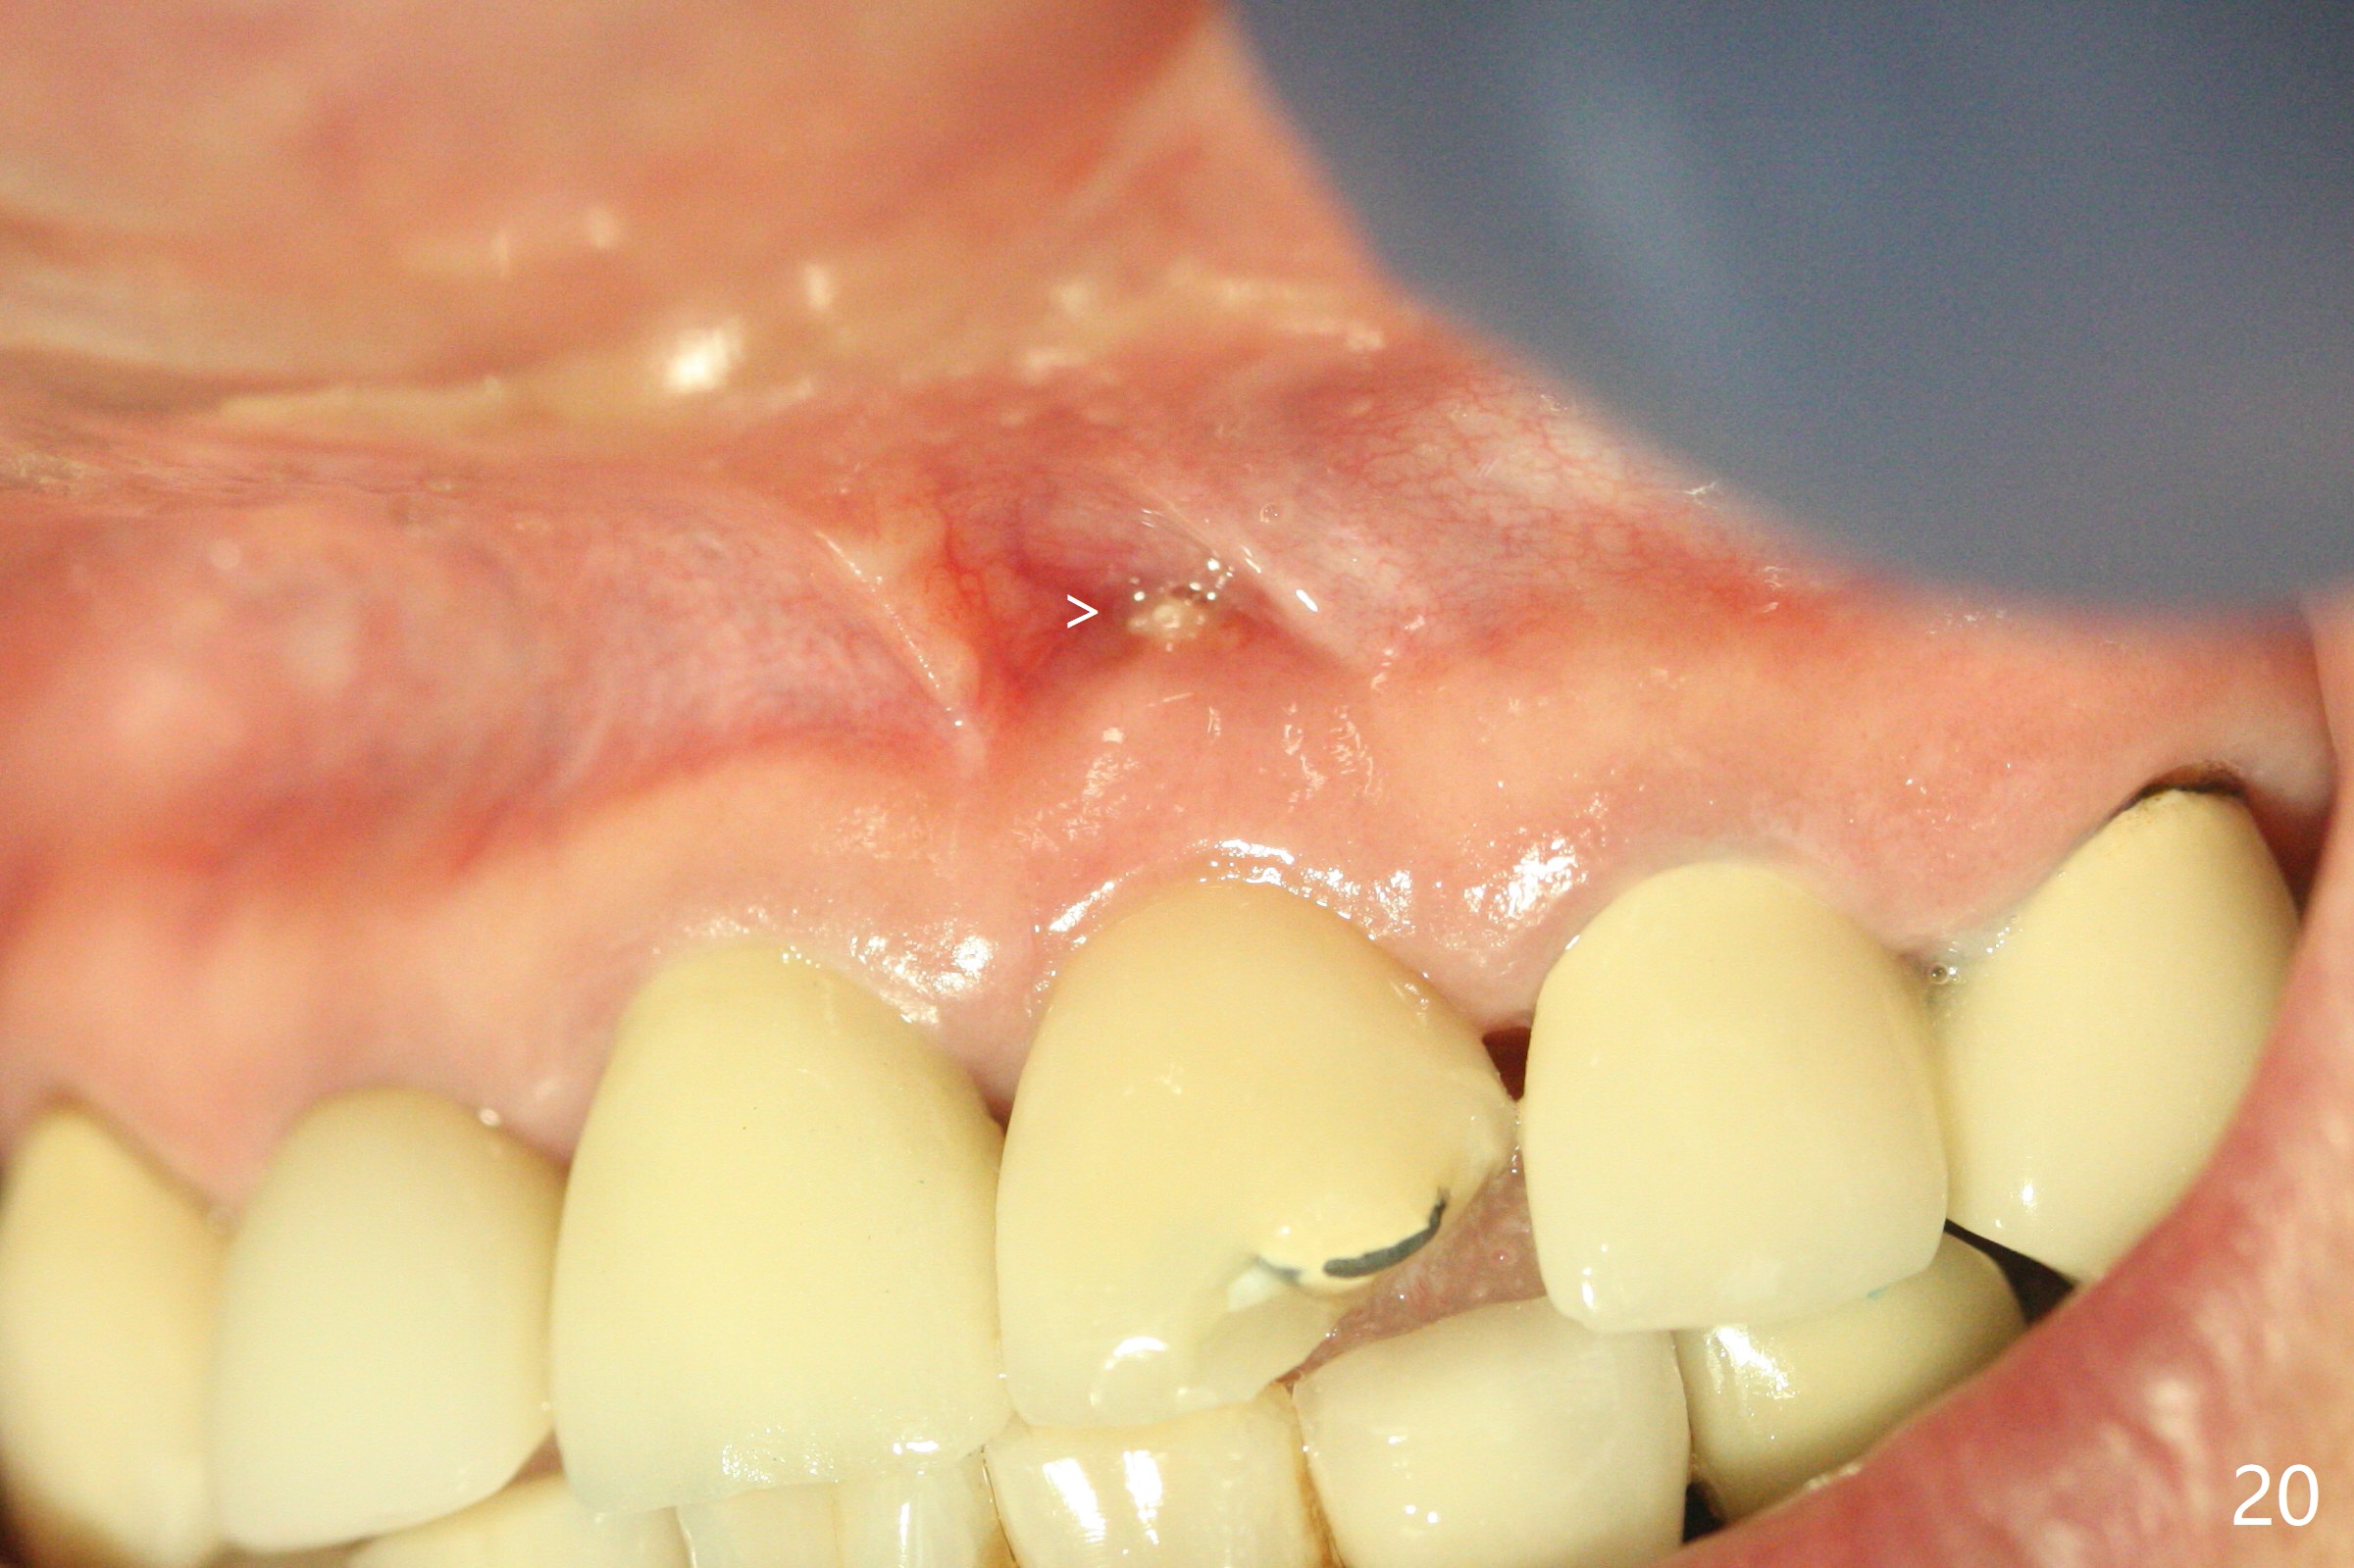

3.8x15 mm Implant with Proximity to

Nasal Floor

The buccal contour at #9 seems to be slightly concave preop (Fig.1,2 (*)). In fact the buccal plate is found to be lost when the tooth is extracted. Osteotomy is initiated as palatal as possible apical, but the occlusion dictates the coronal end of the osteotomy should be buccal, leaving the buccal gap ~ 2 mm for bone graft. The initial osteotomy (18 mm deep) appears to be close to the Incisive Foramen (Fig.3 blue dashed line). The nasal floor appears to be intact when the drill is removed. Subsequent osteotomy is adjusted so that the apical end of the osteotomy moves distal; when a 3.8x15 mm dummy implant is partially placed, there is clearance (Fig.4). It remains so when a definitive implant is seated (Fig.5); Vanilla graft is placed (Fig.5 *) before placement of a 4.5x5.5(3) mm abutment. More allograft is placed when an immediate provisional is fabricated (Fig.6 arrow and *). The gingiva remains to be recessive 1 month postop (Fig.7). It seems to be related to the bulky gingival margin of the provisional (Fig.8 *). After trimming the latter (Fig.9 *), the gingival margin immediately returns close to normal (Fig.10). The gingival margin is even between #8 and 9 two months postop, but the bone graft is exposed apically (Fig.11 ^). It may heals by itself. Otherwise debridement, regraft, PRF and suture are pending. The coronal portion of the socket heals 4 months postop (Fig.12). The gingival cuff forms by the immediate provisional (which is removed for impression) 4 months postop (Fig.13 *). While the full Zirconia crown at #7 remains intact (Fig.14), the PFM at #9 has porcelain chip (Fig.15). It is partially due to the occlusion; while the crown at #7 has clearance with the opposing dentition (Fig.16 *), the one at #9 has no. The access hole at #9 (Fig.17 *) seems to weaken the crown structure. There is no access hole at #7. No solid posterior support is another contributing factor for chip (Fig.18). The buccal plate has mild atrophy at #7 and 9 (Fig.19 *). A piece of bone graft is being expelled apically at #9 (Fig.20 >) and is removed subsequently (Fig.21). Before impression for repacking porcelain, the opposing incisal edge has been shortened (Fig.22 arrows, as compared to Fig.16). Since the ideal access hole is at the incisal edge (Fig.25 black circle), buccal to the existing one (Fig.24 A), the abutment is torqued before the repaired crown is recemented (Fig.23). Finally the crown has occlusal clearance (Fig.26). Porcelain chips again around the access hole of PFM 1.5 years post 2nd cementation. The dense bone at the crest (*) cannot explain why the abutment is not loose, since it remains incompletely seated (>). As it was trimmed short, an angled abutment is used (Fig.28). The coronal end is lingual, while #9/24 is edge to edge. The lingual aspect of the coronal end of the abutment is heavily trimmed to reduce bulkiness. To prevent chip, Zirconium crown will be fabricated in spite of the fact that it does not match the PFM of #8 (potential shade discrepancy). The patient is pleased with the new Zirconia crown (Fig.29).